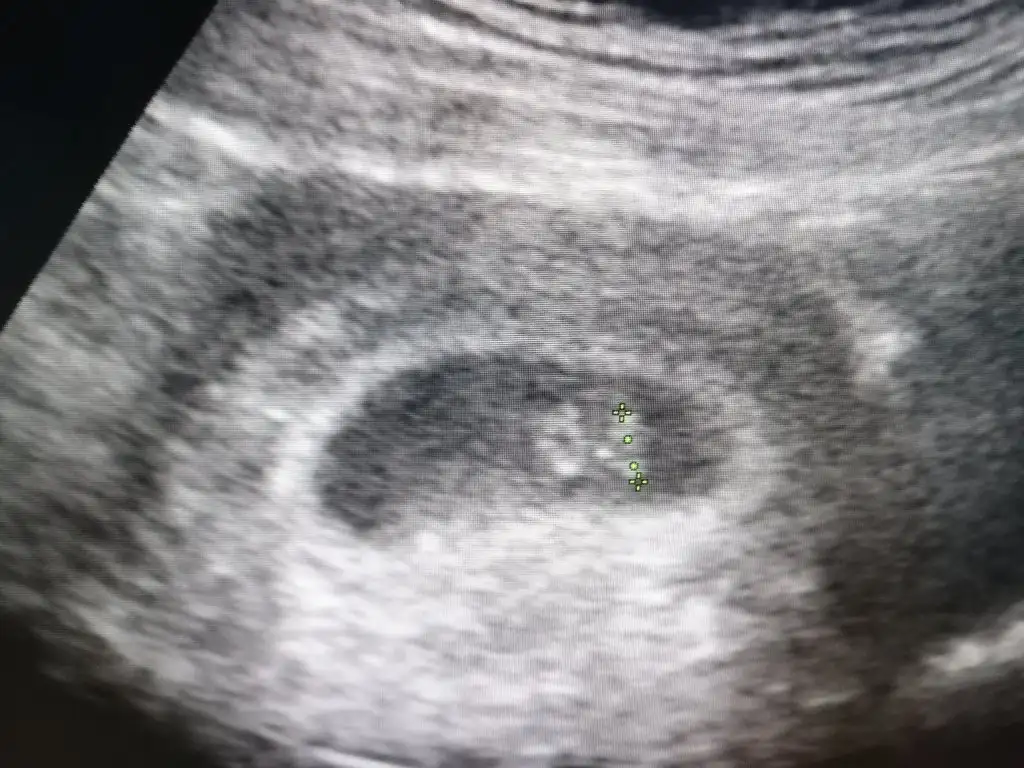

Selam kızlar, sat tarihime göre 5+6 da doktora gittim 5+2 dedi. Doktorun dediği günden hesaplayarak 7+2 de kalp atışı için gittim 6+3 dedi benim 20. Gün yumurtlama bu arada. Fikir olsun stresle bekleyen arkadaşlara. cinsiyet için yorum yapabilir misiniz rica etsem

Eklentiler

• IMG_20210127_092033.webp

56,3 KB · Görüntüleme: 122